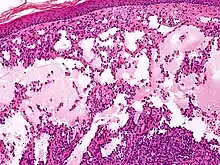

Proliferating lymphangioma, H&E stain. Sometimes endothelial cells begin to divide excessively.

In 1976, Whimster studied the pathogenesis of lymphangioma circumscriptum, finding lymphatic cisterns in the deep subcutaneous plane are separated from the normal network of lymph vessels. They communicate with the superficial lymph vesicles through vertical, dilated lymph channels. Whimster theorized the cisterns might come from a primitive lymph sac that failed to connect with the rest of the lymphatic system during embryonic development.

A thick coat of muscle fibers that cause rhythmic contractions line the sequestered primitive sacs. Rhythmic contractions increase the intramural pressure, causing dilated channels to come from the walls of the cisterns toward the skin. He suggested that the vesicles seen in lymphangioma circumscriptum are outpouchings of these dilated projecting vessels. Lymphatic and radiographic studies support Whimsters observations. Such studies reveal that big cisterns extend deeply into the skin and beyond the clinical lesions. Lymphangiomas that are deep in the dermis show no evidence of communication with the regular lymphatics. The cause for the failure of lymph sacs to connect with the lymphatic system is not known.[4]

Microscopically, the vesicles in lymphangioma circumscriptum are greatly dilated lymph channels that cause the papillary dermis to expand. They may be associated with acanthosis and hyperkeratosis. There are many channels in the upper dermis which often extend to the subcutis (the deeper layer of the dermis, containing mostly fat and connective tissue). The deeper vessels have large calibers with thick walls which contain smooth muscle. The lumen is filled with lymphatic fluid, but often contains red blood cells, lymphocytes, macrophages, and neutrophils. The channels are lined with flat endothelial cells. The interstitium has many lymphoid cells and shows evidence of fibroplasia (the formation of fibrous tissue). Nodules (A small mass of tissue or aggregation of cells) in cavernous lymphangioma are large, irregular channels in the reticular dermis and subcutaneous tissue that are lined by a single layer of endothelial cells. Also an incomplete layer of smooth muscle also lines the walls of these channels. The stroma consists of loose connective tissue with a lot of inflammatory cells. These tumors usually penetrate muscle. Cystic hygroma is indistinguishable from cavernous lymphangiomas on histology.[4]